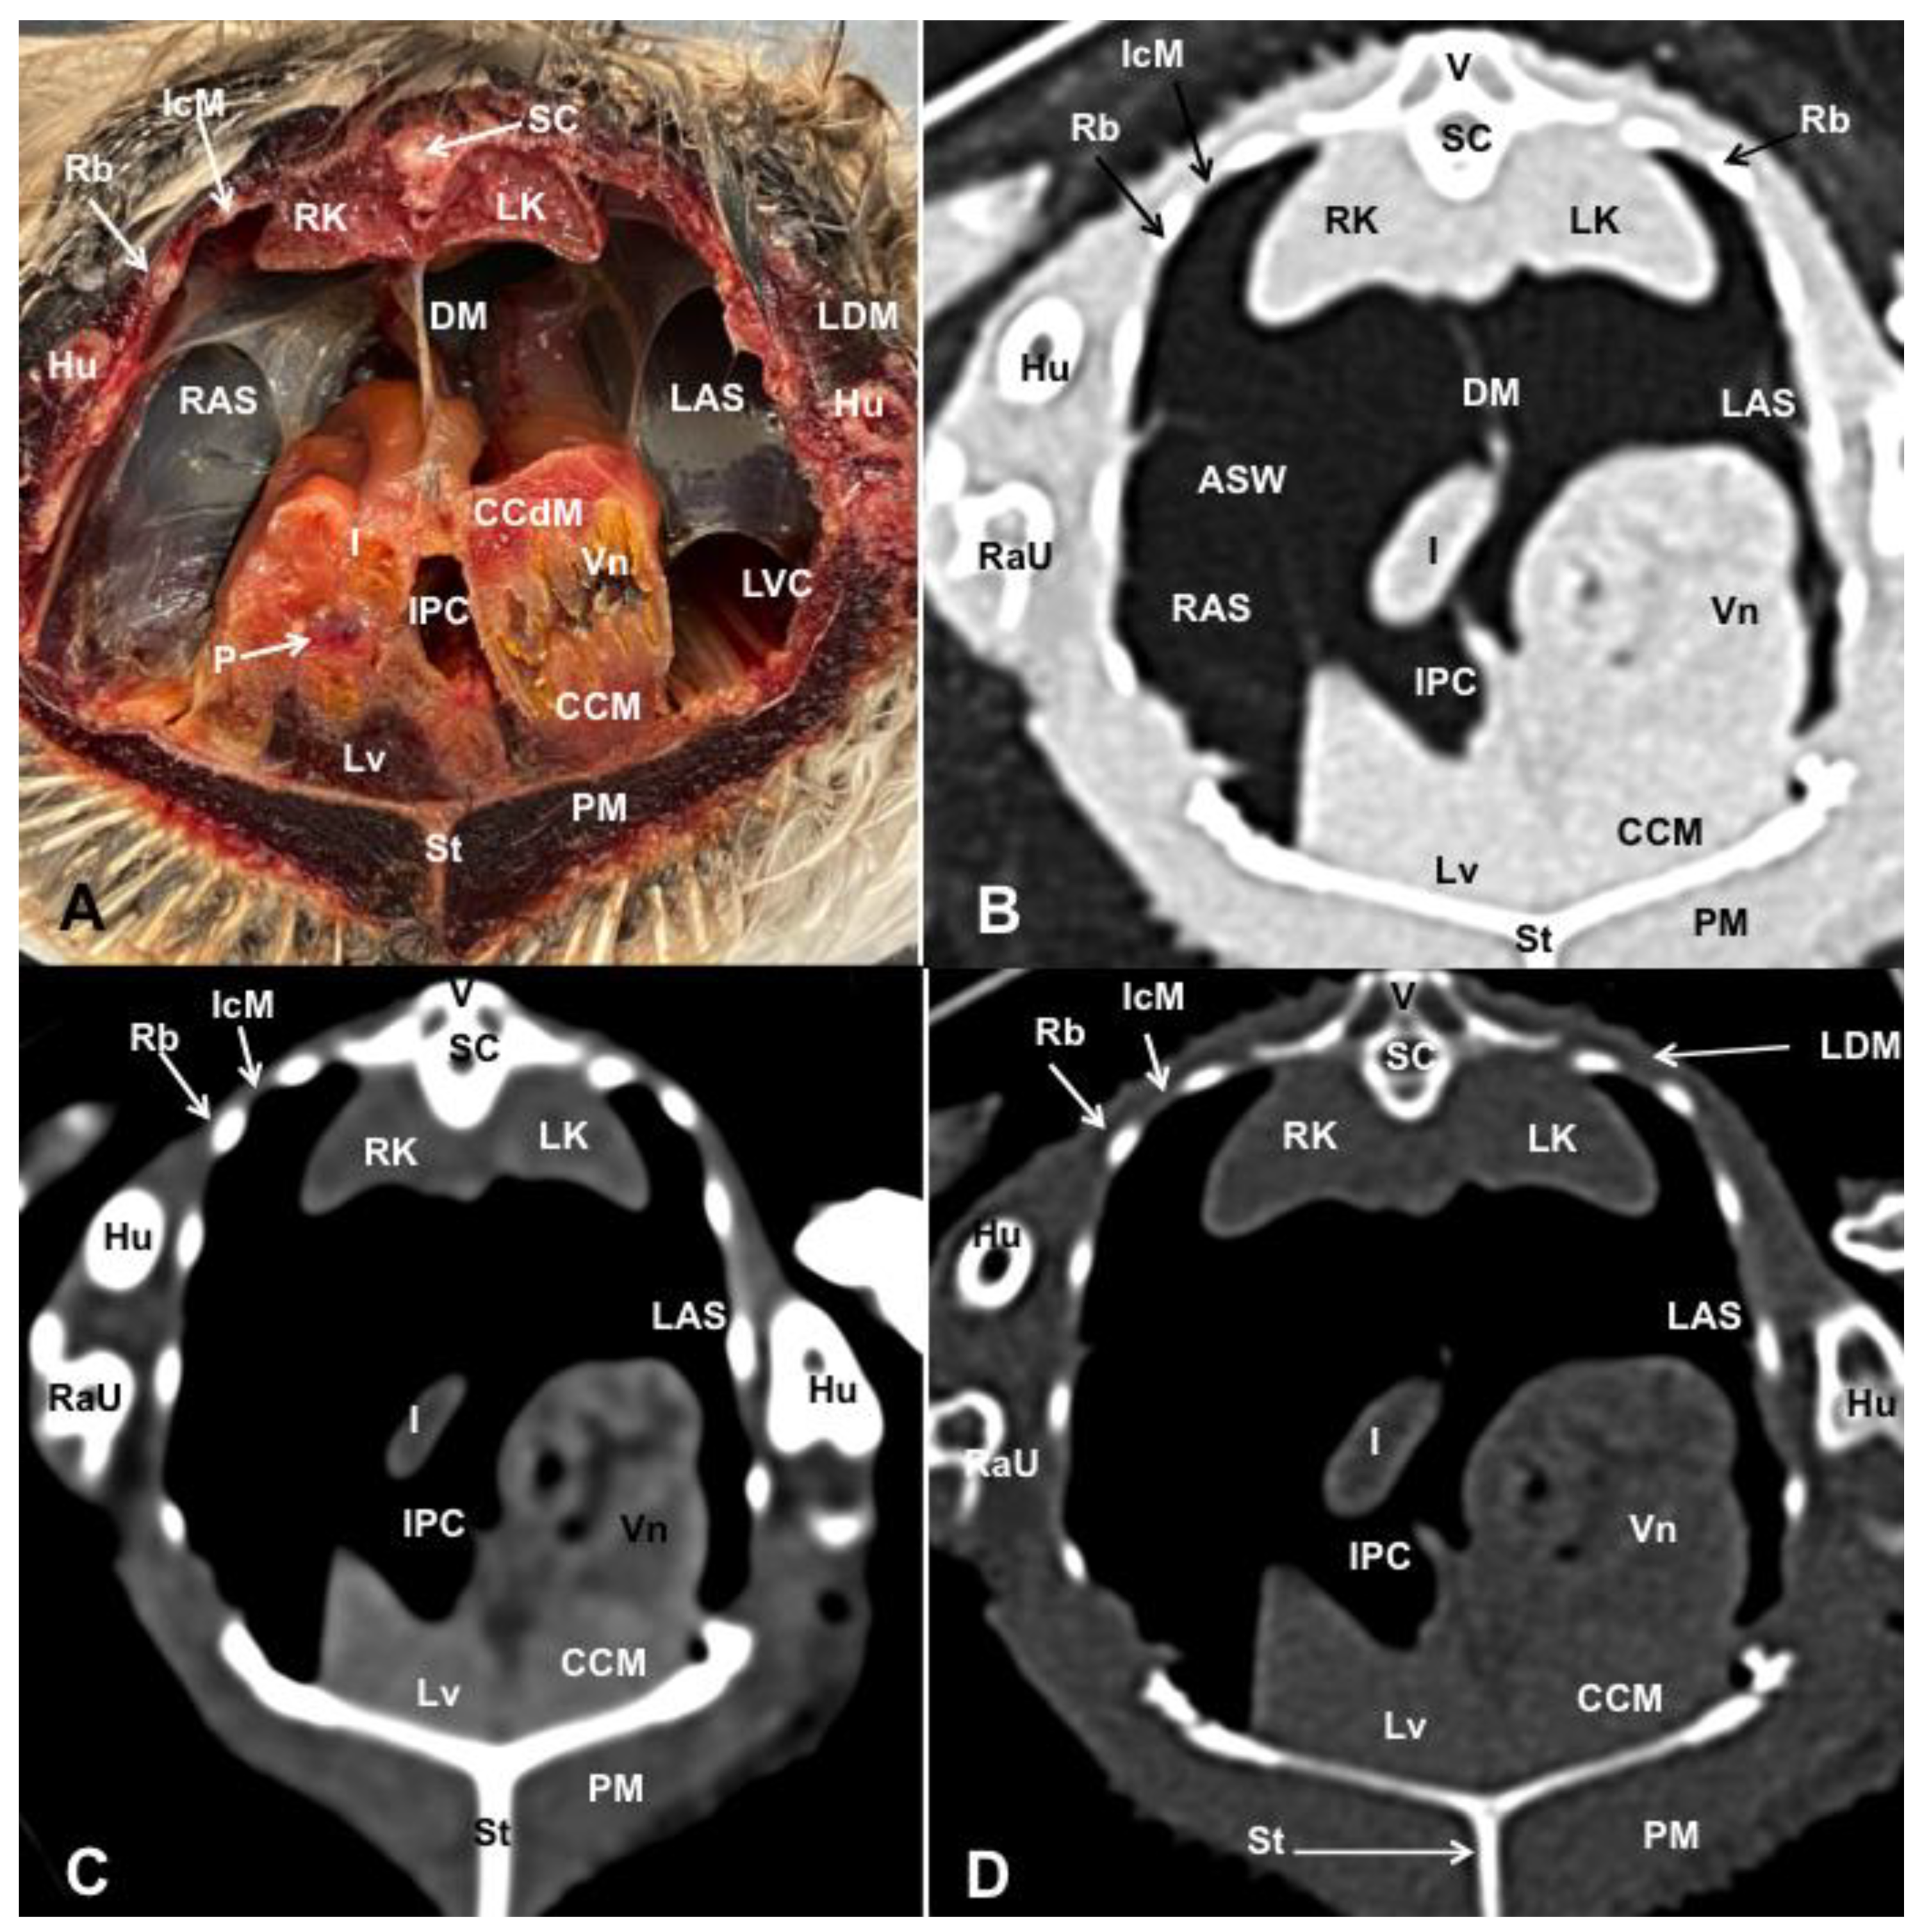

3. Results

3.1. Anatomical Dissections and Cross-Sections

3.2. Computed Tomography Images